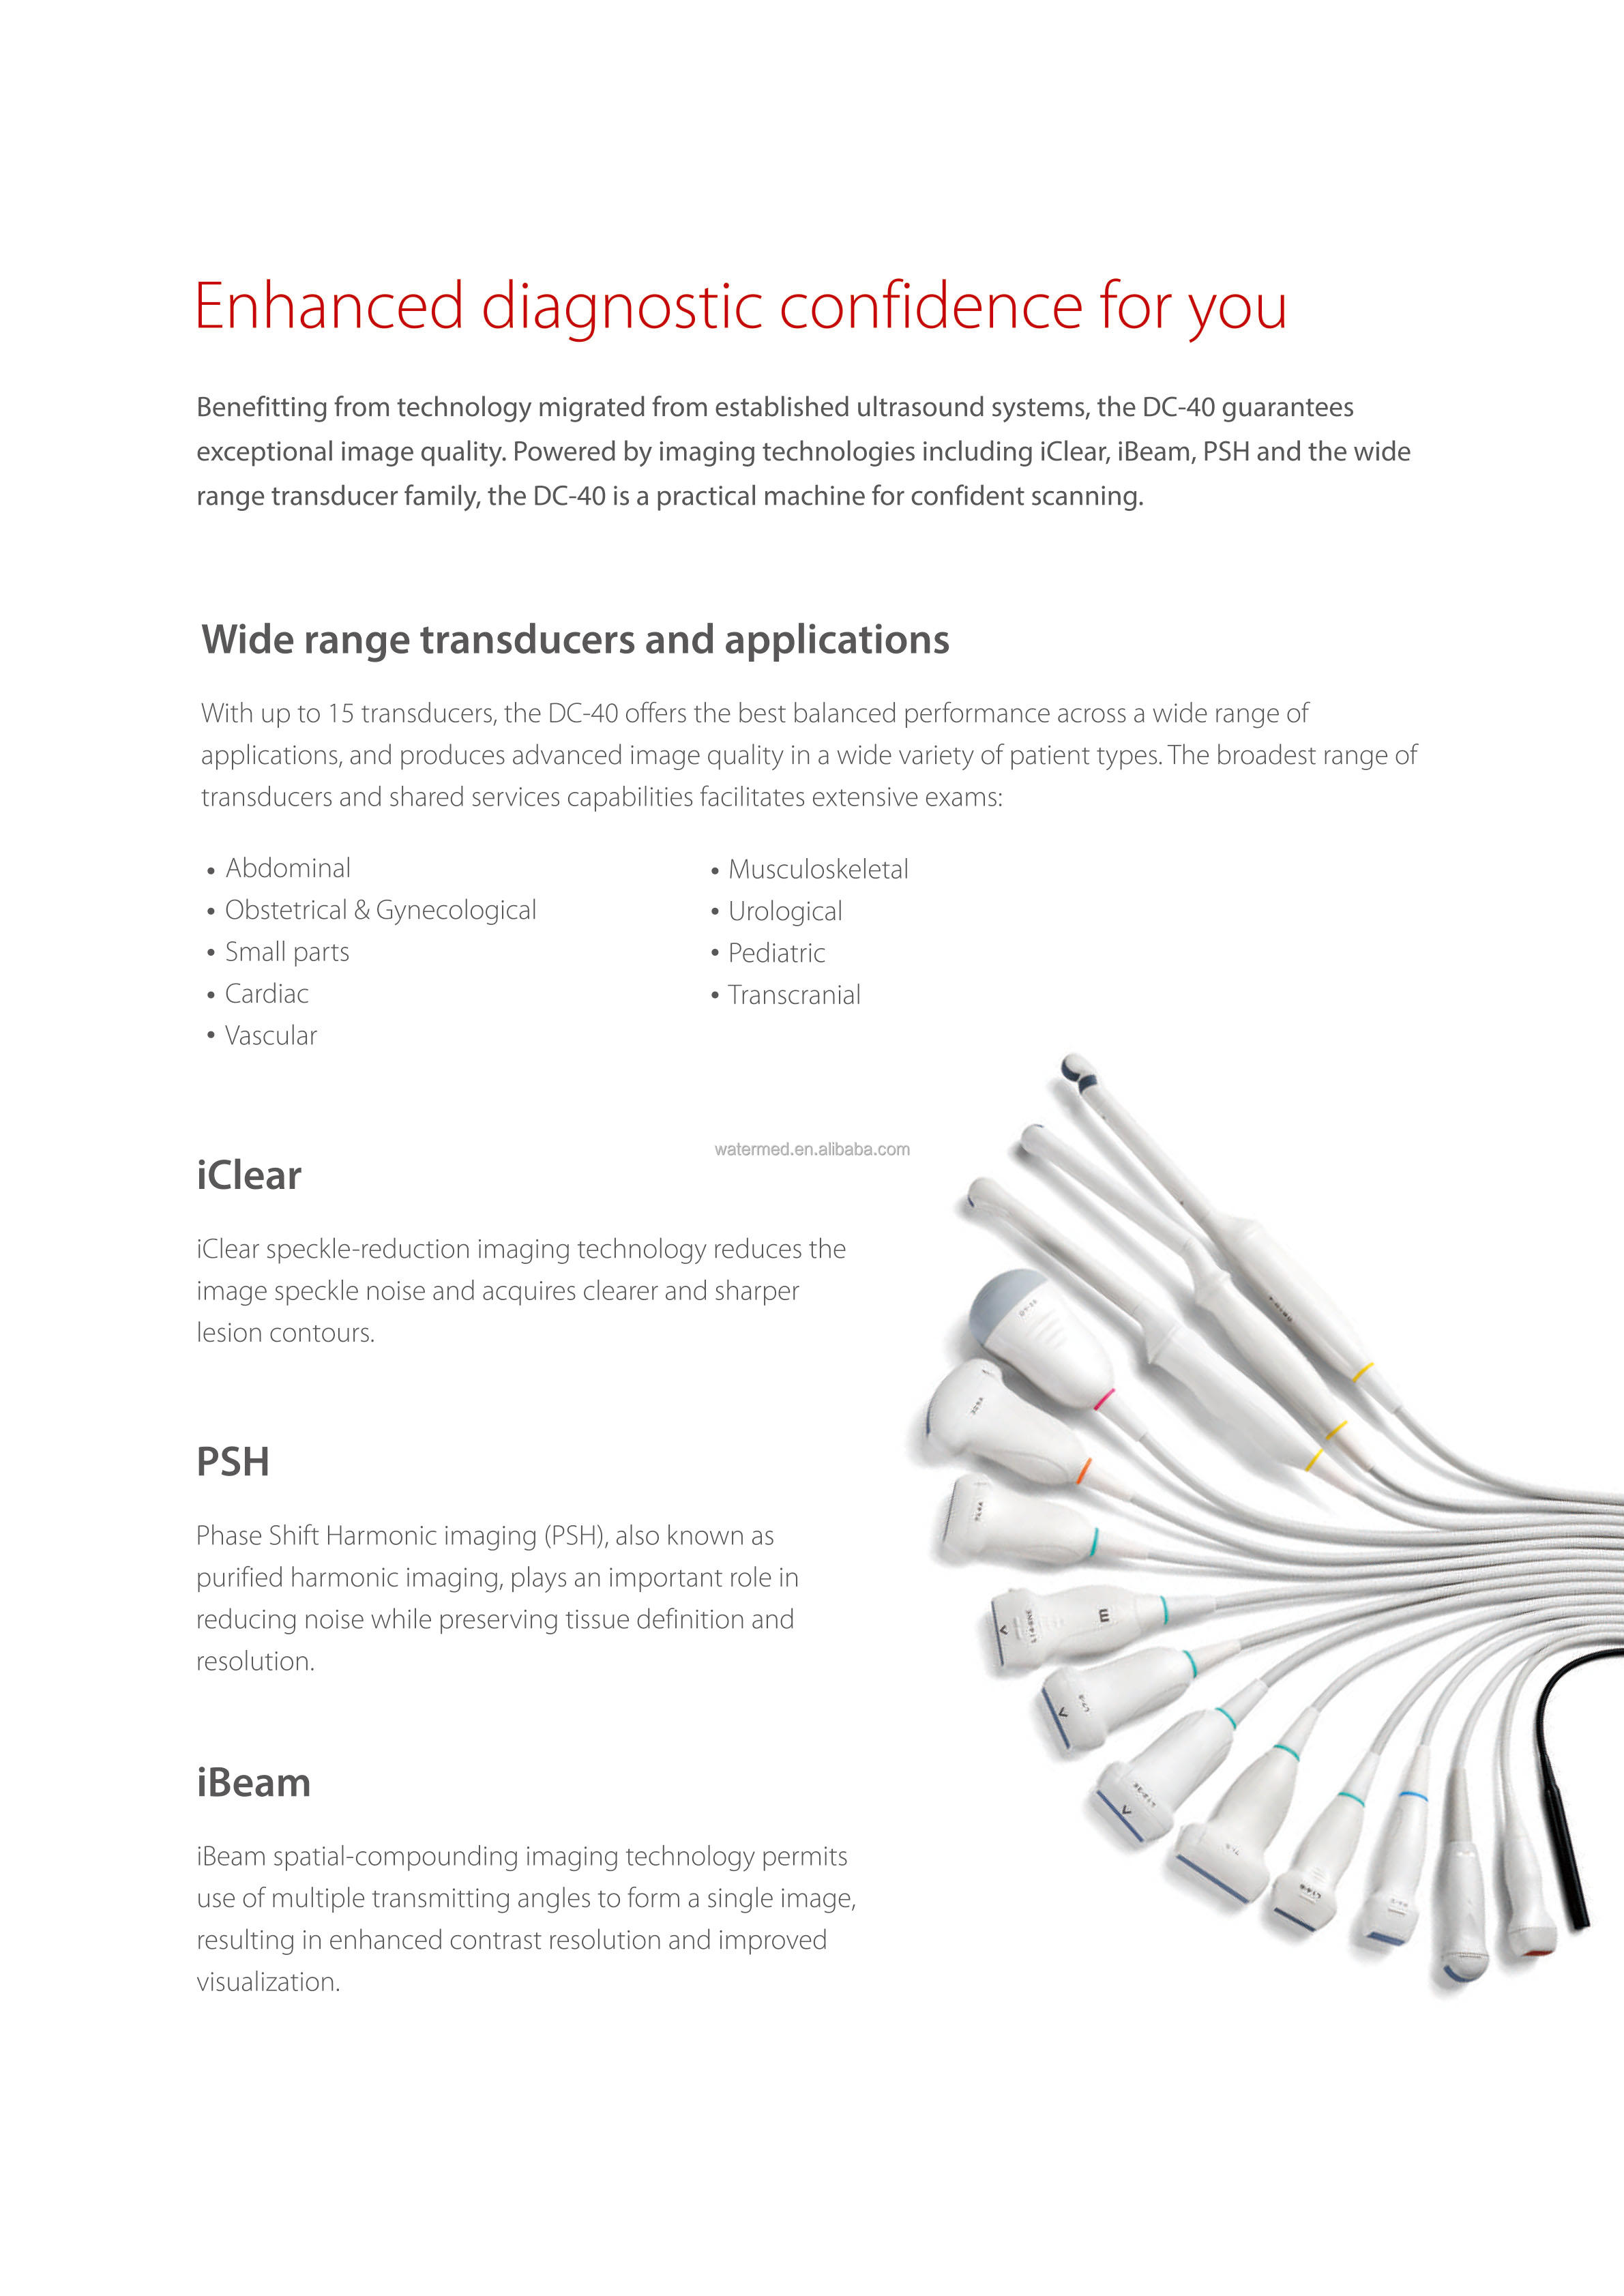

Mindray DC-40 application:

• abdomen

• Obstetrics

• Gynecology

• IVF (in vitro fertilization)

• Cardiology

• small parts

• Urology

• Blood vessel

• Pediatrics

• Emergency Medicine

• nerves

• other